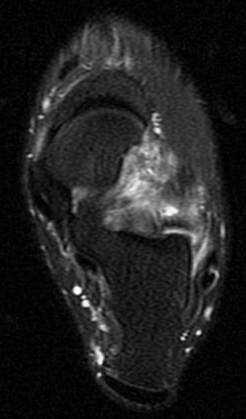

36 yo M s/p ankle sprain 7 months ago

Marked edema and scarring in the tarsal sinus. Has healed sprains of the ankle ligaments with scar remodeling (not shown). You can see where the ongoing pain is by the oil marker. I insist on having pain markers when possible. Reference article.

sinus tarsi syndrome ( RID3222 )